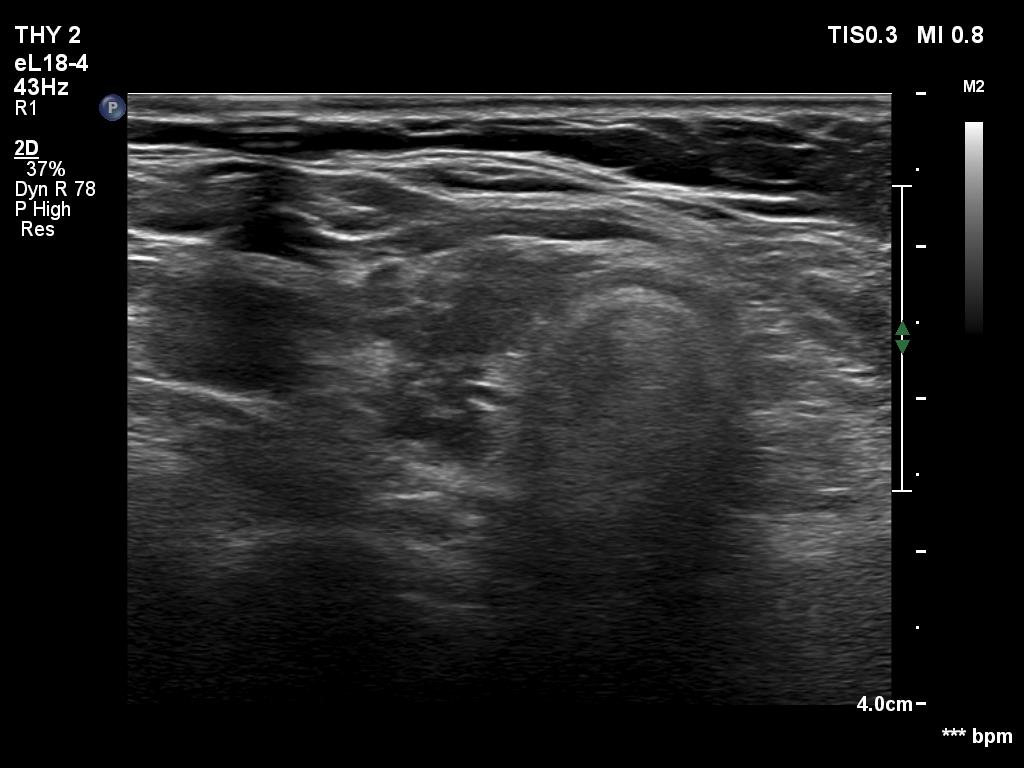

Ultrasonography. The thyroid was mainly composed of hypoechoic islets which floated in less hypoechoic background. These lesions had irregular, lobulated margins and showed no vascularity.

Comment. The presentation was not entirely characteristic of Hashimoto's thyroiditis. Nevertheless, the multiplicity of the lesions, the irregular borders and the moderately hypoechoic non-lesional part of the lobe all argued for being these lesions not true nodules but more active foci of thyroiditis.